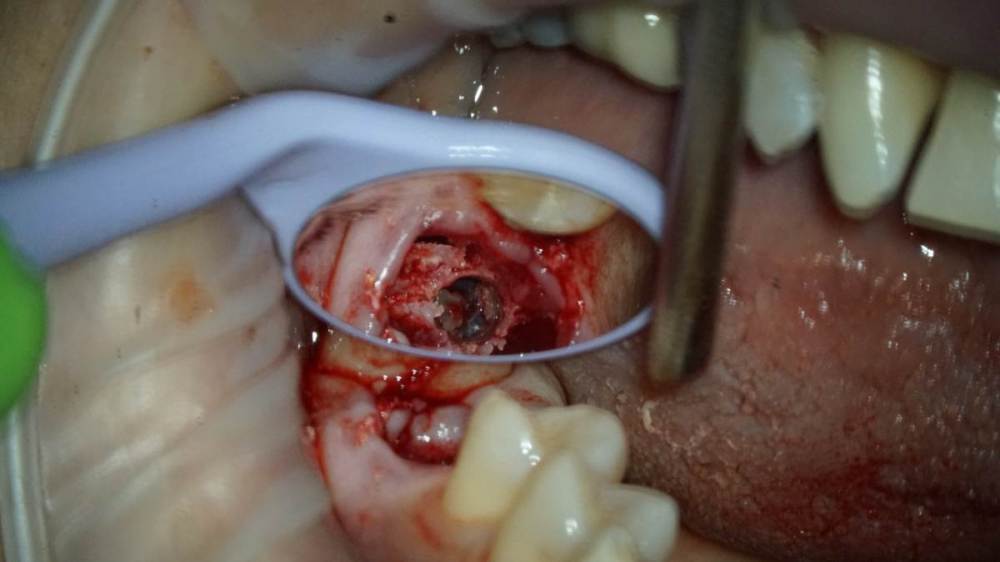

TIGER Опубликовано 4 февраля, 2022 Поделиться Опубликовано 4 февраля, 2022 (изменено) Видео отслойки мембраныКоллеги доброго дня!Вашему вниманию закрытый синус-лифт под визульным контролем через операционный микроскоп)С появлением скопа в практике стало больше закрытых синусов)остальные методы не позволяют контролировать операционное поле при отслоение мембраны (на видео ниже запечатлена отслойка) MAH01810.MP4 Изменено 4 февраля, 2022 пользователем TIGER 3 1 Ссылка на комментарий